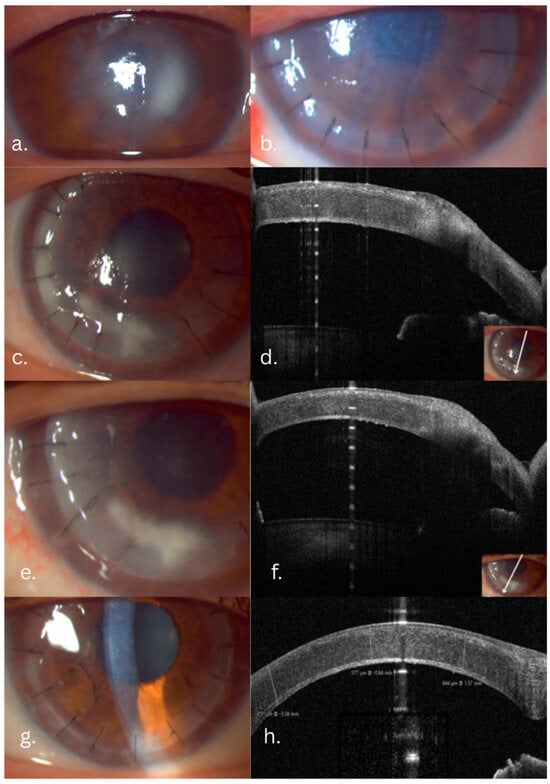

2.1. Case 1—Candida Keratitis with Acanthamoeba Coinfection

2.2. Case 2—Filamentous Fungal Keratitis